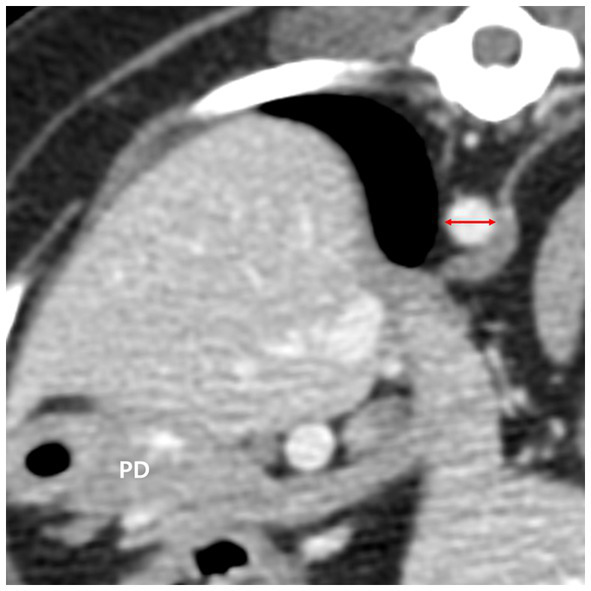

The diameter of the aorta (Ao) was measured horizontally (right lateral to left lateral) at the level where the pancreatic body was measured on the transverse plane (Figure 4). Additionally, the ratio of the pancreatic thickness measured on transverse plane to aorta (P/Ao), short dimension to aorta (S/Ao) ratio, and long dimension to aorta (L/Ao) ratio were calculated. The short and long dimension are measurements taken in a cross-sectional image (oblique sagittal or transverse MPR plane) through the long axis of the pancreas.

Figure 4

The diameter of the aorta (red double arrow) was measured in the transverse plane horizontally at the level where the pancreatic body (PD) was measured. PD, pancreatic body.